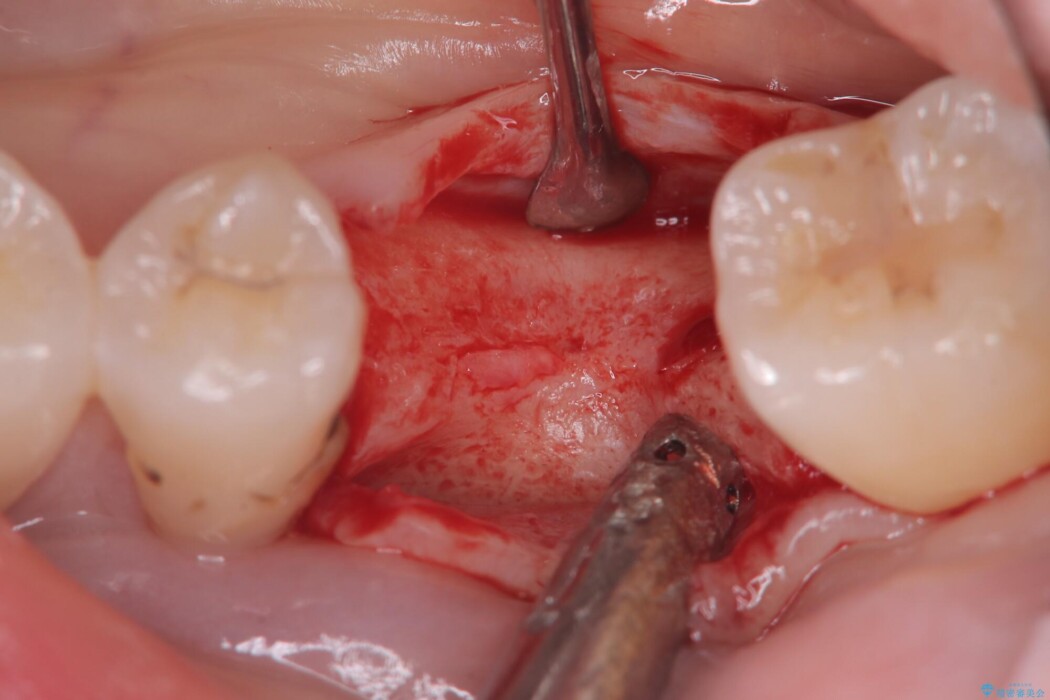

左下奥歯の抜歯後、長期間放置していたために、周囲の骨が吸収してしまいました。 特に垂直的な高さが不足しており、通常の術式ではインプラント埋入が難しい状態でした。

精密検査の結果、高さに制限はあるが厚みは十分に確保されていることが確認されました。

骨を増やす治療は行わず、残っている骨を最大限に活用し治療を行うこととしました。

一般的に、骨が少ない場所への埋入は高度な技術を要しますが、今回は適切なサイズ(8.5mm)を選択し、埋入する深さを緻密にコントロールすることで、周囲の神経や重要な組織を傷つけることなく安全に処置を完了しました。